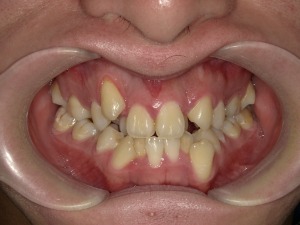

1. 重度の叢生(歯のデコボコ)

「叢生(そうせい)」とは、歯がガタガタに並んでいる状態を指します。特に顎の大きさに対して歯のサイズが大きすぎる場合、歯がきれいに並ぶスペースが足りずに重なって生えてしまうことがあります。

軽度の叢生であれば、非抜歯で歯列を広げたり奥歯を後ろに移動させたりして対応できますが、中等度〜重度の場合は抜歯によってスペースを確保する必要が出てきます。